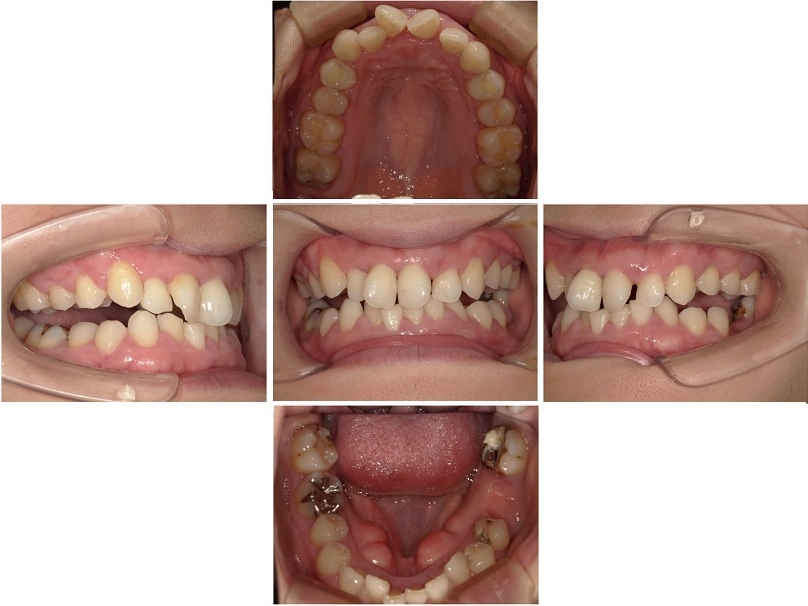

患者様ご自身には痛みや違和感などの自覚症状はありませんでしたが、全体的に歯ぐきの赤みや腫れが強くみられます。

歯と歯ぐきの境目にある溝の深さである歯周ポケットを測定したところ、健康な状態では2〜3ミリ程度であるのに対し、今回は4〜8ミリです。

これらの検査結果から、お口全体に中等度から重度の歯周病があると考えられました。

画像をクリックすると拡大・詳細コメントを確認いただけます